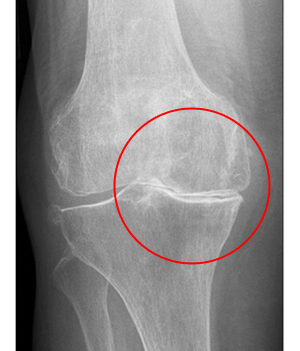

<¹«¸­°üÀý¿° X-RAY / MRI>

¹«¸­¿¬°ñÀÇ ¼Õ»ó ¶Ç´Â ÅðÇ༺ º¯È­·Î ÀÎÇØ °üÀýÀ» ÀÌ·ç´Â »À¿Í ÀÎ´ë µî¿¡ ¼Õ»óµîÀ¸·Î ÀÎÇÏ¿© ¿°Áõ°ú ÅëÁõÀÌ »ý±â´Â °æ¿ì¸¦ ¹«¸­ °üÀý¿°À̶ó°í ÇÕ´Ï´Ù. ¹«¸­°üÀý¿°Àº 55¼¼ ÀÌ»óÀÎ °æ¿ì¿¡´Â ¾à 80£¥, 75¼¼ÀÎ °æ¿ì¿¡´Â °ÅÀÇ Àü Àα¸¿¡ ¹ßº´Çϰí ÀÖ°í ³²¼ºº¸´Ù´Â ¿©¼º¿¡°Ô ´õ ¸¹ÀÌ ³ªÅ¸³ª¸ç ±× Á¤µµµµ ½ÉÇÕ´Ï´Ù. ¶ÇÇÑ ºñ¸¸ÁõÀÌ ÀÖ´Â °æ¿ì³ª °ú°Å¿¡ ±³Åë»ç°íŬ¸®´ÐÀ̳ª ¿Ü»óÀ¸·Î ÀÎÇÏ¿© »À³ª °üÀýÀÌ ´ÙÃÆ´ø °æ¿ì, ¼±Ãµ¼º ±âÇüÀÌ ÀÖ´Â °æ¿ì, »À ´ë»ç¿¡ ÀÌ»óÀÌ ÀÖ´Â °æ¿ì, Á÷¾÷ ¶Ç´Â Ãë¹Ì·Î ÇÑ °üÀýÀ» °è¼ÓÇØ¼­ ¹«¸®ÇÏ°Ô »ç¿ëÇÏ´Â °æ¿ì¿¡µµ Àß ¹ß»ýÇÏ°Ô µË´Ï´Ù.